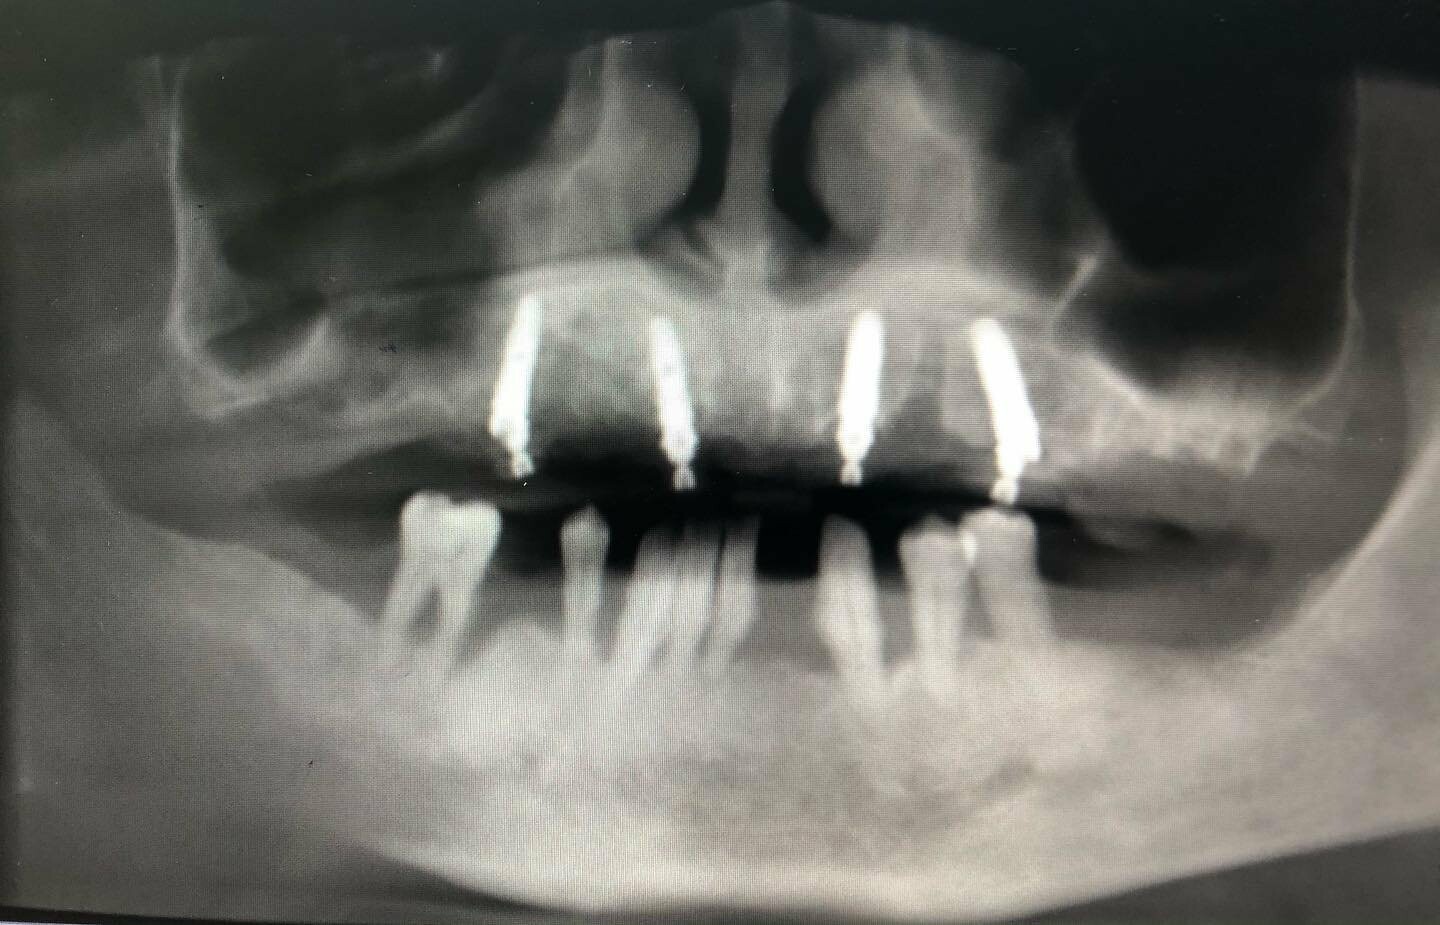

Временные конструкции пациента с генерализованный пародонтитом с применением методики All-on-4 (все на 4-х)

Врач @motordantist